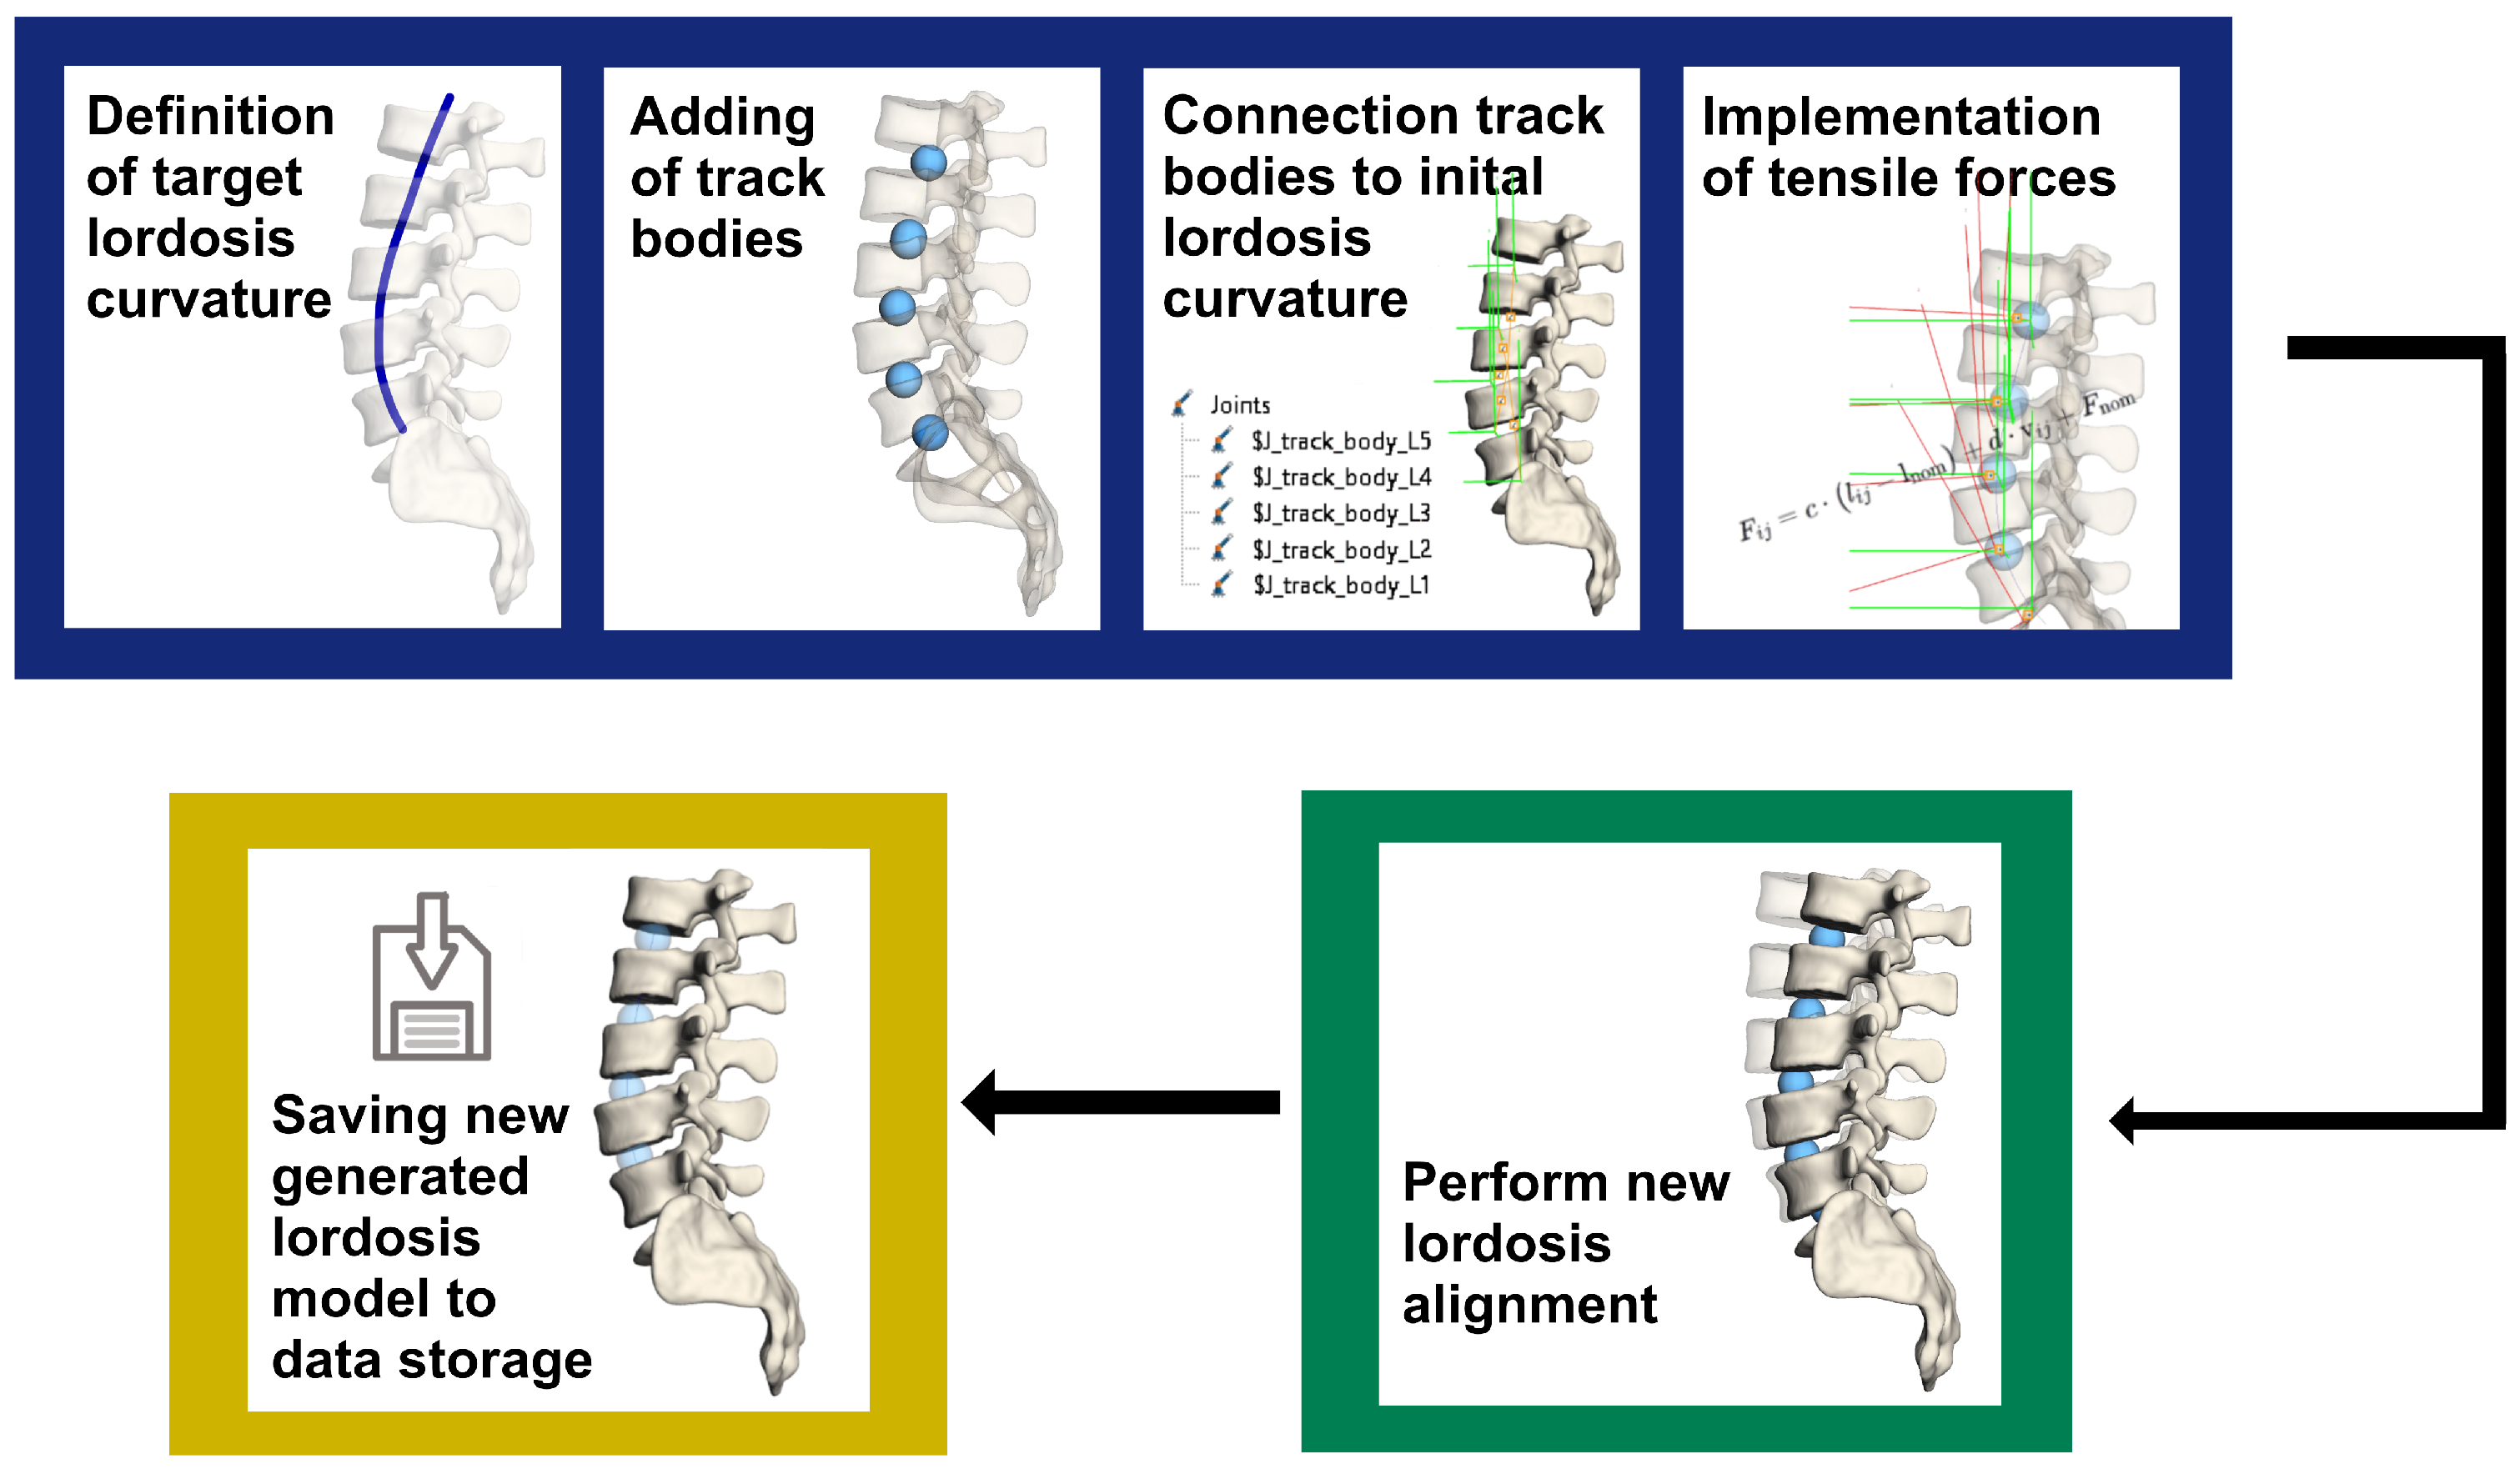

2.2. Lordosis Curvature Fitting for Simulation Model

3.2. Creation of New Lordosis Model from 3D Curvature